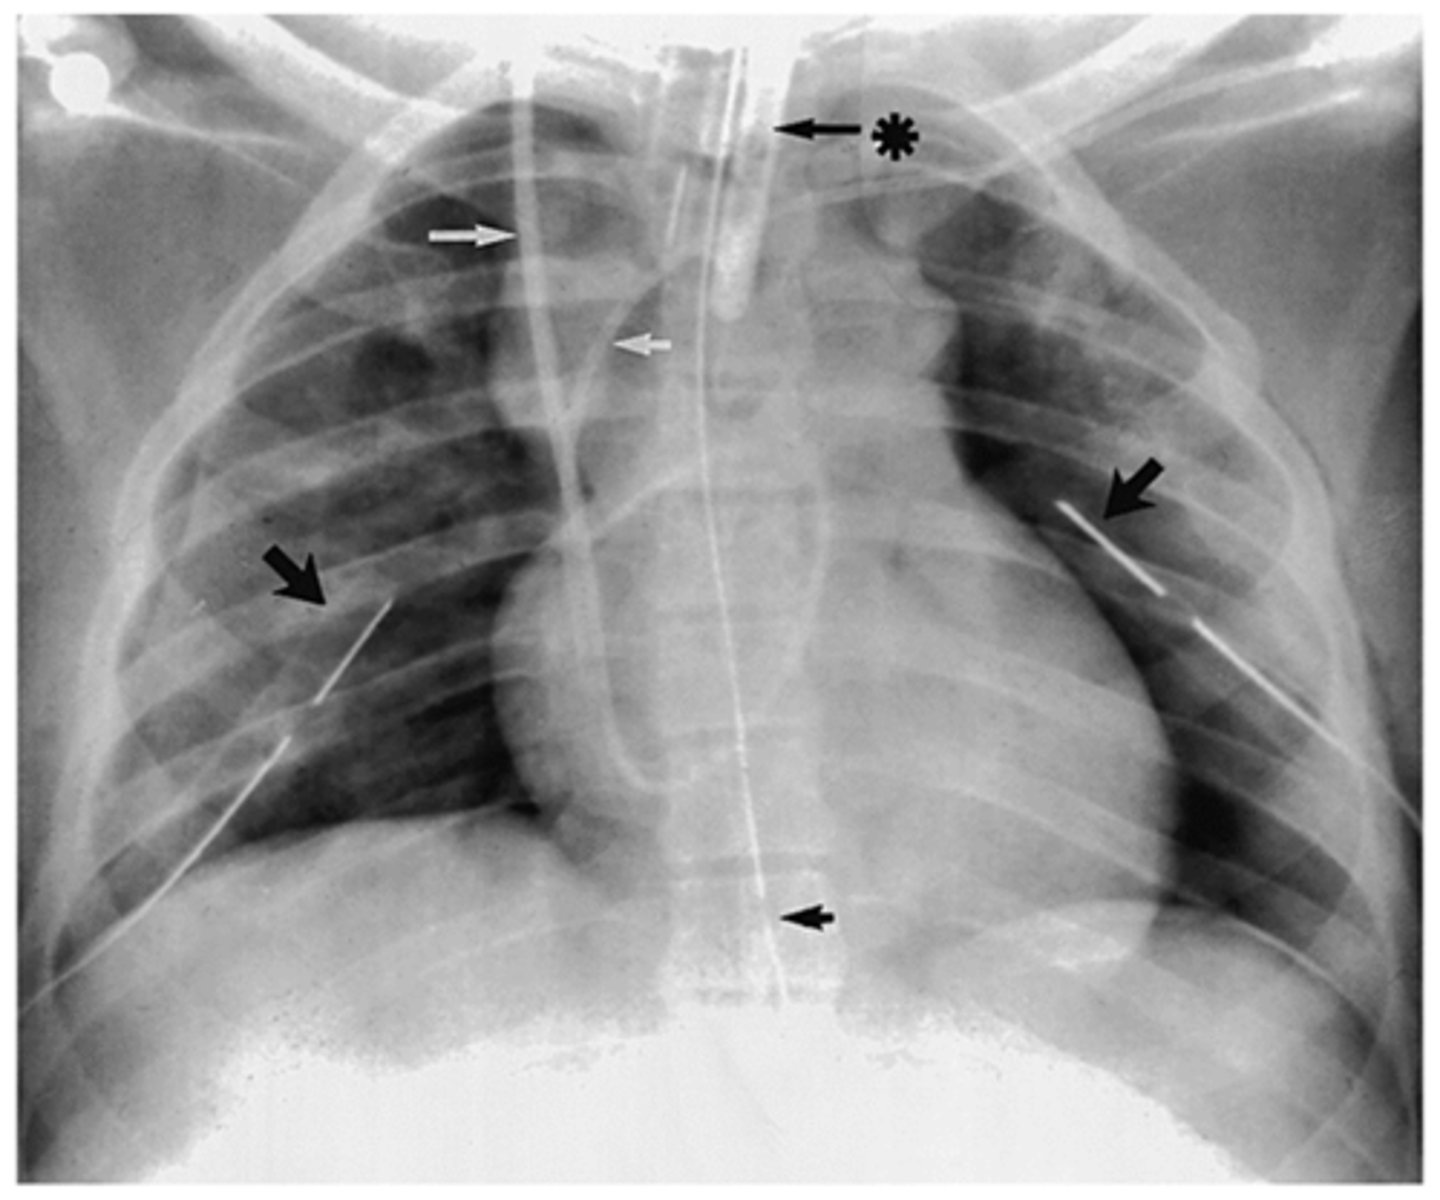

CXR of tracheal intubation with ETT

What is going on in this CXR?

Pulmonary artery catheter (tip at right midlung near hilum)

What is goin going on in this CXR?

Nasogastric feeding tube (NG tube) placement (ensure tip places at stomach or small bowel)

Chest tube (tip of tube should be posterior and near apex of lung for drainage)